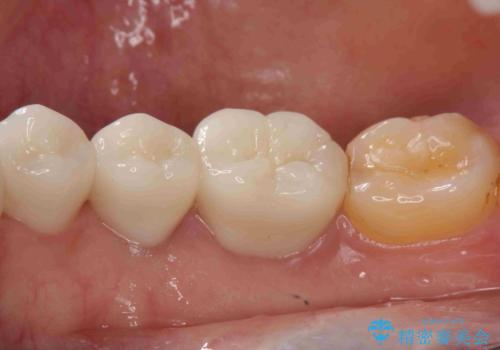

大きい虫歯 根管治療〜オールセラミッククラウン